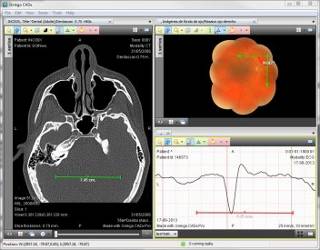

Digital Imaging and Communications in Medicine (DICOM) is a medical imaging format used for X-ray, CT scans and MRI images. DICOM is a wrapper file format encapsulating JPEG images (lossy or lossless variants). Here are a few DICOM file viewers for Linux: (many also can also view volumetric CT and MRI 3D scans)

| Software | Description |

|---|---|

| AMIDE

| Supports DICOM and volumetric medical image viewing. Features include support for multiple color-maps, thresholding, 3D and volume rendering, filtering, fly-through, image data-set alignment,... GTK+ based GUI. GPLv2 |

| Ginkgo CADx

| Advanced 3D tools, worklist support, multiplanar reconstruction, fusion, ... Commercial application but open source. Free and supported versions (which also has extra capabilities). Ginkgo CADx Sourceforge page |

| MIPAV

| MIPAV is a medical image viewer for PET, MRI, CT and microscopy 2D and 3D data-sets. Includes analysis tools to support biomedical data research (Talairach space brain mapping, FRAP, FRET), filtering (spatial, noise, thresholding, Isotropic diffusion), ... Java based cross platform application. Source and binaries available. Funded and developed by the National Institute of Health Center for Information Technology (CIT) Online manual |

| Aeskulap

| This medical image viewer can query and fetch DICOM images from network archive PACS nodes. Open source based on gtkmm, glademm and gconfmm. Tutorial (pdf) Download not currently available?? |

| MRIcron

| Supports multiple image layers, image intensities, grey-scales and color schemes with threshold control. Also supports volume rendering (voxels) with various viewing angles and slices. GTK2 based GUI. (Follow-on to MRIcro) |

| XnView | Commercial application. A general image viewer which also happens to support viewing DICOM images. |